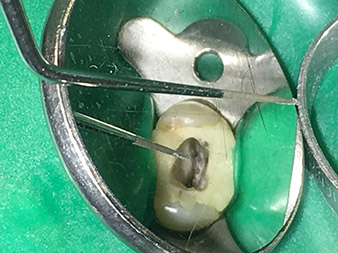

Dr. Nouraie: Der Einsatz von Ultraschallspitzen ermöglicht einen gezielten, schonenden und minimalen Substanzabtrag an der gewünschten Stelle (wie z.B. bei der Freilegung der Kanaleingänge, beim Abrunden des Kavitätenbodens und Freipräparieren von abgebrochenen Instrumenten oder Stiften sowie beim Bearbeiten der koronalen Kanalabschnitte).

Die Glättung und Abrundung der Kanalübergänge kann gezielter erfolgen als mit Hilfe von Bohrern. Insbesondere die Aktivierung der Spülflüssigkeit bringt enorme Vorteile, die durch andere Instrumente nicht gewährleistet werden kann. Mit Hilfe der Spezialinstrumente von W&H können ganz neue Indikationen minimalinvasiv durchgeführt werden, wie z.B. eine Revision von abgebrochenen Spitzen und Stiften.

Für alle Indikationen im Kanal sollten Sehhilfen in Form von Lupe oder noch besser in Form eines Mikroskops eingesetzt werden.